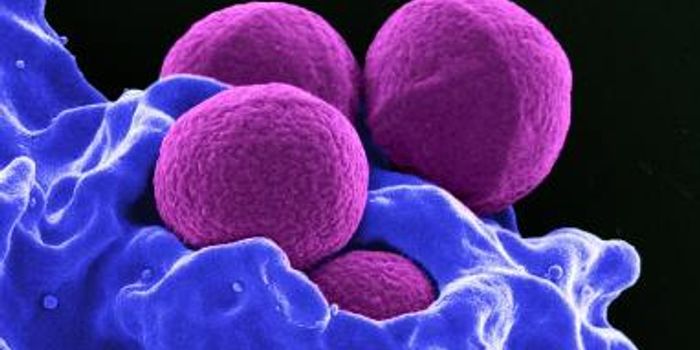

MAY 26, 2016MicrobiologyIn March 2015, President Obama released The National Action Plan for Combating Antibiotic-Resistant Bacteria. It is inte ...

JAN 31, 2016MicrobiologyResearchers at the University of Notre Dame identified the mechanism by which Streptococcus pyogenes, also known as Grou ...

APR 08, 2018MicrobiologyThis new kind of compound acts in a unique way, and may be effective against drug-resistant bacteria.

SEP 20, 2022MicrobiologyDrug resistant bacterial infections are expected to increase, and these dangerous illnesses already claim the lives of t ...

DEC 27, 2018MicrobiologyIt's no secret that antibiotic resistance is a problem that already poses a serious threat to public health, and it's ex ...